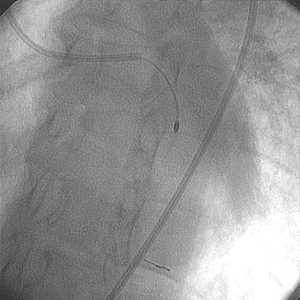

Sistema post ROTABLATOR

El equipo médico decidió usar el sistema Rotablator. Se atravesó la lesión con una oliva de 1,75 mm sin dificultad sobre la cuerda guía RotaWire™ Floppy.

• Luego de usar el sistema Rotablator™, se dilató la lesión con un balón para ACTP de 4,0 mm x 20 mm.